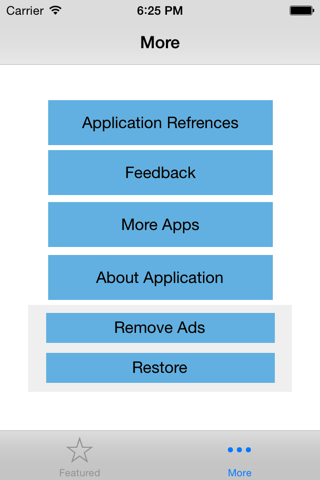

Child-Pugh (CP) classification was originally designed to determine the risk of portocaval shunt surgery in cirrhotic patients. CP classification provides mortality risk with abdominal surgery, survival rates and a likelihood of developing complications secondary to underlying cirrhosis. The input variables include serum bilirubin, serum albumin, presence of ascites or encephalopathy and prothrombin time. The minimum CP score is 5 whereas the maximum possible score is 15. A score of 5-6 is classified as class A indicating well compensated cirrhosis, whereas a score of 7-9 is class B with significant functional compromise, and a score of 10-15 is a class C with decompensated cirrhosis. This application implements the CP classification system and assigns a score and stage based on the user provided input.